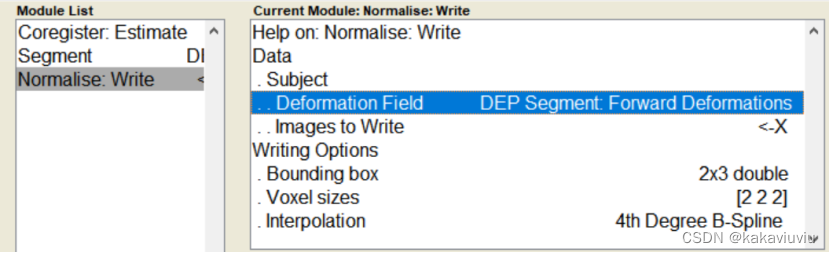

3.个体fMRI---应用第二步的形变场--->标准空间fMRI(Normaliz&Write)

再选择normalise

点dependency

修改boundingbox和体素3 3 3

Run

生成wra开头的文件